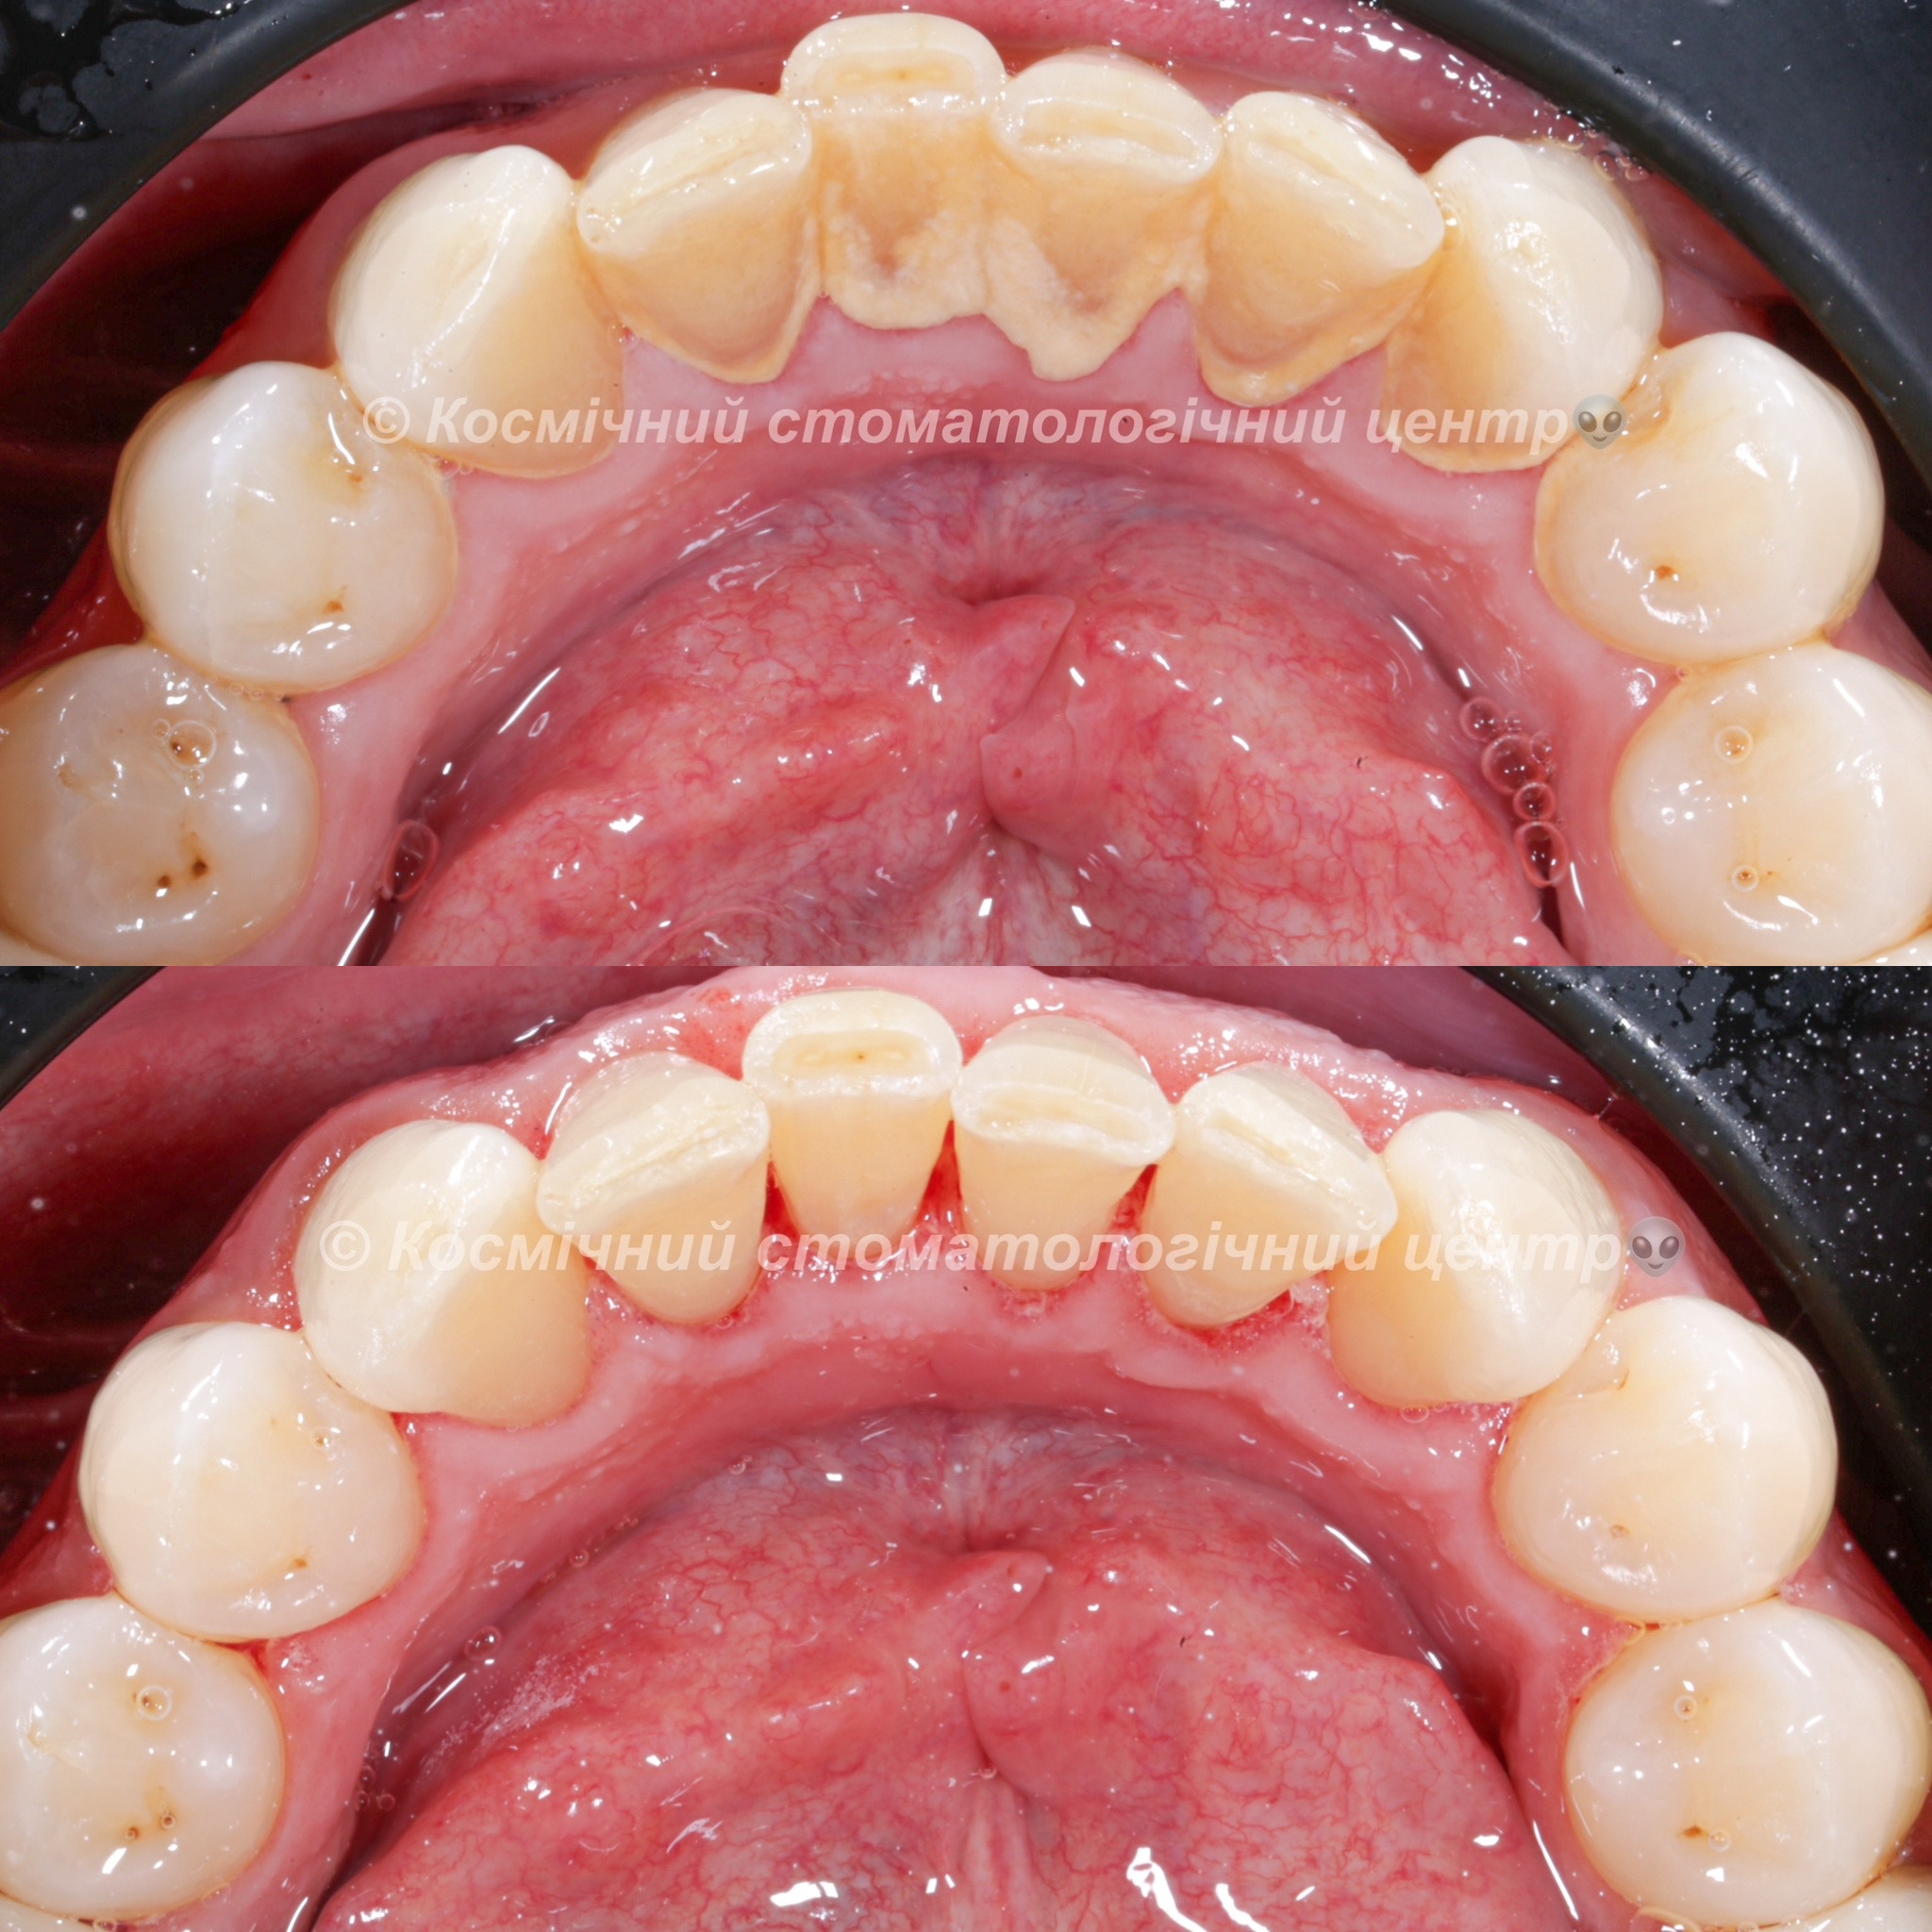

Галерея

Професійна гігієна (чистка) зубів складається з кількох етапів

• Комп'ютерна анестезія у разі підвищеної чутливості зубів.

• Зняття каменю ультразвуковим девайсом SIRONA (Німеччина) та звуковим наконечником KAVO (Німеччина) з електронним регулюванням потужності.

• Зняття каменю у важкодоступних місцях пародонтальними кюретами HU-Friedy.

• Зняття нальоту гігієнічними перлинами KaVo PROPHY pearls SUPRAGINGIVAL CALCIUM CARBONATE в індивідуальних пакуваннях із ароматом на вибір: персик, апельсин, м'ята, чорна смородина та нейтральний смак.

• Полірування швейцарською пастою Proxyt Ivoclar Vivadent для блиску та природної білизни.

• Діагностика прихованих захворювань ясен (скрінінг-тест).

• Покриття зубів фтористим лаком у місцях підвищеної чутливості;

• Ремінералізуюча терапія;

Ультразвукова чистка зубів

Зубний камінь, в залежності від місця утворення, поділяється на над- та підясенний. Найбільшу небезпеку для здоров'я зубів становить другий тип, адже це дуже сприятливе середовище для шкідливих бактерій.

При проведенні професійної гігієни застосувується ультразвуковий скалер, що дозволяе видалити зубний камінь разом з хвороботворними бактеріями з підясенних кишень.

Повітряно-абразивна чистка зубів (Air Flow)

Завдяки піскоструменевому апарату з технологією Air Flow, який використовуючи тиск повітря та води, подає на зубну емаль спеціальний абразивний склад, зуби можна очистити не лише від м’якого нальоту, а й від пігменту. Для видалення нальоту, в Космічній стоматології Драганчука ми використовуємо KaVo prophy pearls supragingival calcium carbonateneutral.

Чистка зубів щіточками та пастами

Фінальний етап професійної гігієни - полірування спеціальними щіточками та пастою, щоб усунути мікротріщини та шорохуватості, що виникли після чистки та видалити залишки нальоту, що могли в них залишитись. Це дозволяє суттєво уповільнити формування нових відкладень.

Полірування зубної емалі гумками

Кінцеве полірування поверхні зубів проводиться із застосуванням різних насадок, зокрема спеціальних гумок, що надає зубам ідеальної гладкості та блиску. Спеціальні гумові насадки відмінно справляться з наданням естетичної довершеності твоїй посмішці.